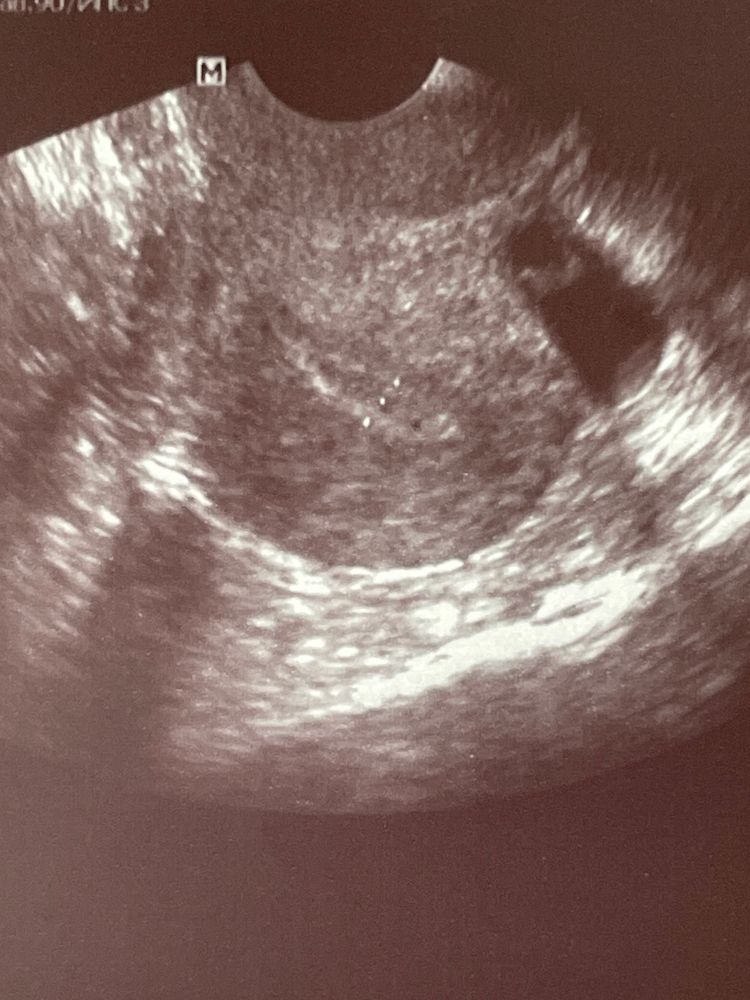

3 фото. Образование 13 мм, с пристеночной структурой 3*4 мм - эндометриома? (3 мая)